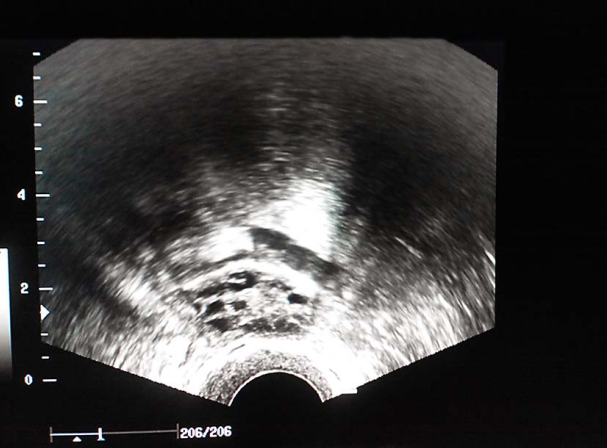

(1)超声检查:推荐使用经阴道超声,明确子宫和卵巢大小、位置、形态、有无异常结节或囊、实性包块回声,评估卵巢储备。还可监测优势卵泡发育情况及同期子宫内膜厚度和形态分型。

卵泡生长发育监测(窦卵泡期) 卵泡生长发育监测(卵泡中期) 卵泡生长发育监测(卵泡晚期)

卵泡生长发育监测(排卵前期) 输卵管积水超声表现 输卵管积水超声表现